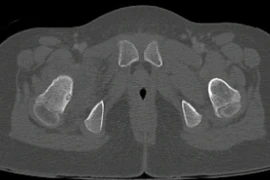

(khoahocdoisong.vn) - Chỉ nghĩ con bị đau xương tuổi dậy thì nào ngờ trẻ 12 tuổi bị u máu khổng lồ phá hủy nửa cánh xương chậu và đe dọa tính mạng. Nhờ kỹ thuật nút mạch và ghép xương, các bác sĩ tại hai bệnh viện kết hợp đã loại bỏ thành công khối u máu và trám xương thành công cho trẻ.